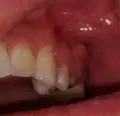

Подскажите, пожалуйста. Болела десна около недели, незначительно. Позже образовался какой-то шарик, похожий на прыщик. А после, во время еды что-то стало мешать и вот появилось непонятное новообразование из десны. На ощупь твердое, беспокоит во время приема пищи.

Подскажите, что это может быть?

Очень сложно определить, но все Ваши симптомы говорят и свищевом выходе. То есть, на верхушках зуба имеется воспалительный процесс.